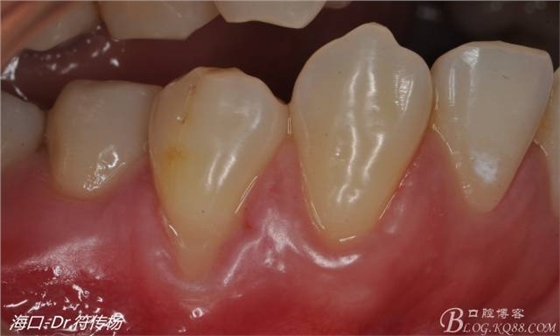

從病例圖片我們可以看到44牙頰側(cè)牙齦出現(xiàn)明顯萎縮

術(shù)前評(píng)估:退縮的齦緣在MGJ冠方 近遠(yuǎn)中牙槽嵴頂高度正常屬于Miller -Ι類牙齦退縮 所有術(shù)后可以完全覆蓋